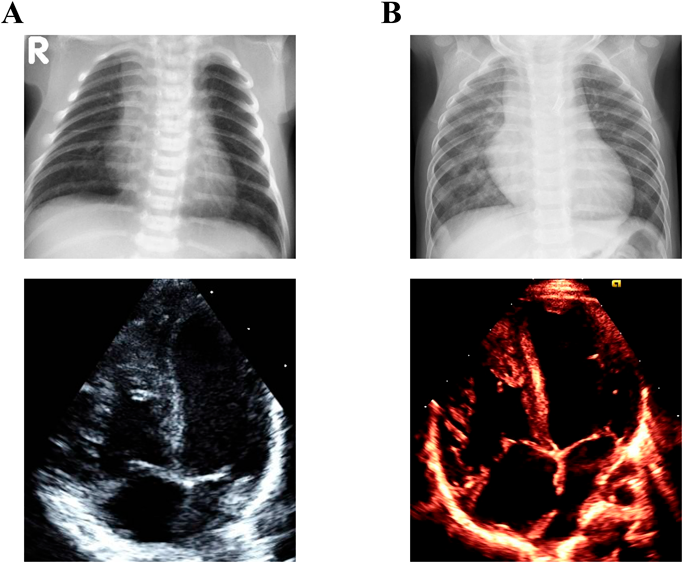

Fig. 5 Case 3: Chest X-ray and four chamber view of two-dimensional transthoracic echocardiography

A) pre first DS (day 3): CTR is 51% and RVEDAI is 15.9 cm2/m2. B) pre Rastelli procedure (8 month): CTR is 64% and RVEDAI is 23.2 cm2/m2. CTR: cardio-thoracic ratio, RVEDAI: right ventricular end-diastolic area index